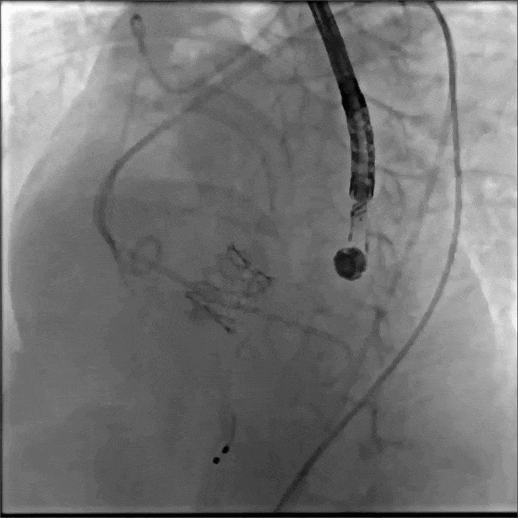

术中造影